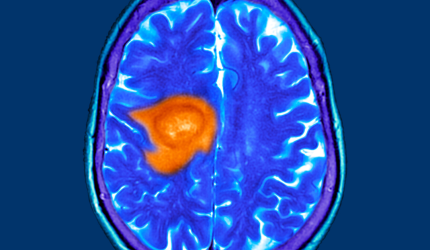

Os tumores de cabeça e pescoço representam uma variedade de cânceres que afetam a boca, laringe (caixa de voz), faringe (garganta), nariz, seios paranasais, ou glândulas salivares. A compreensão das opções de tratamento disponíveis é crucial para pacientes e familiares que enfrentam esses diagnósticos desafiadores.

Quando falamos sobre tumores de cabeça e pescoço, estamos nos referindo a um grupo de cânceres que afetam diversas áreas desta região do corpo, incluindo a garganta, laringe, nariz, seios paranasais, e boca. Reconhecer os sinais e sintomas iniciais desses tumores é crucial para o diagnóstico precoce e um tratamento eficaz.Ler mais